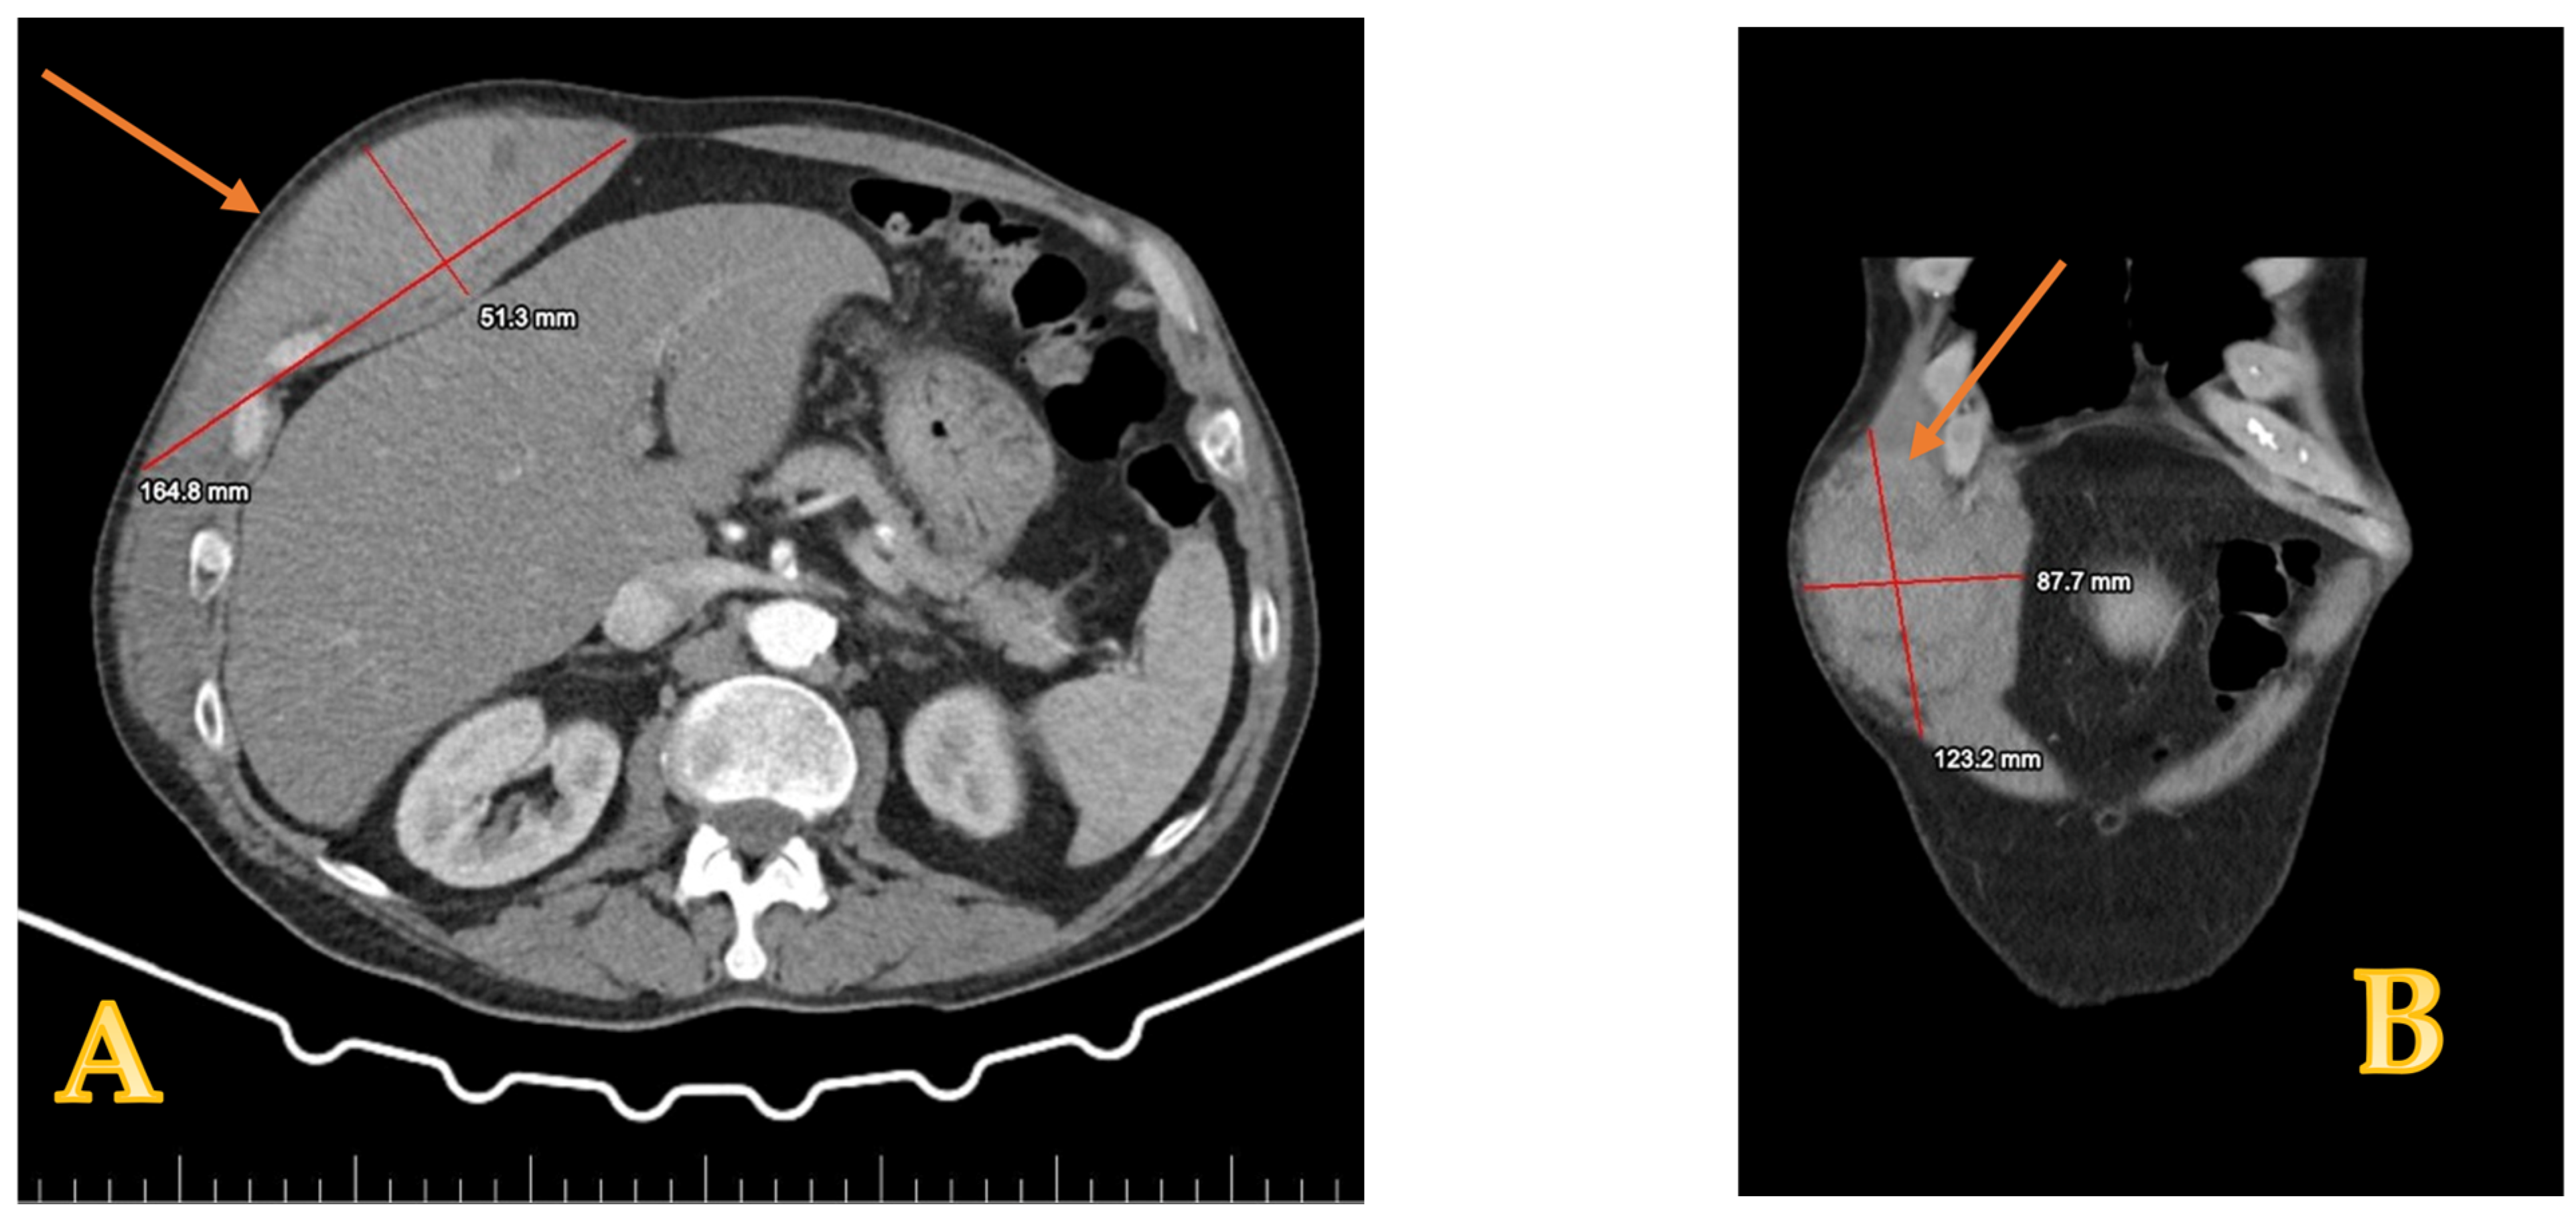

2. Case Presentation